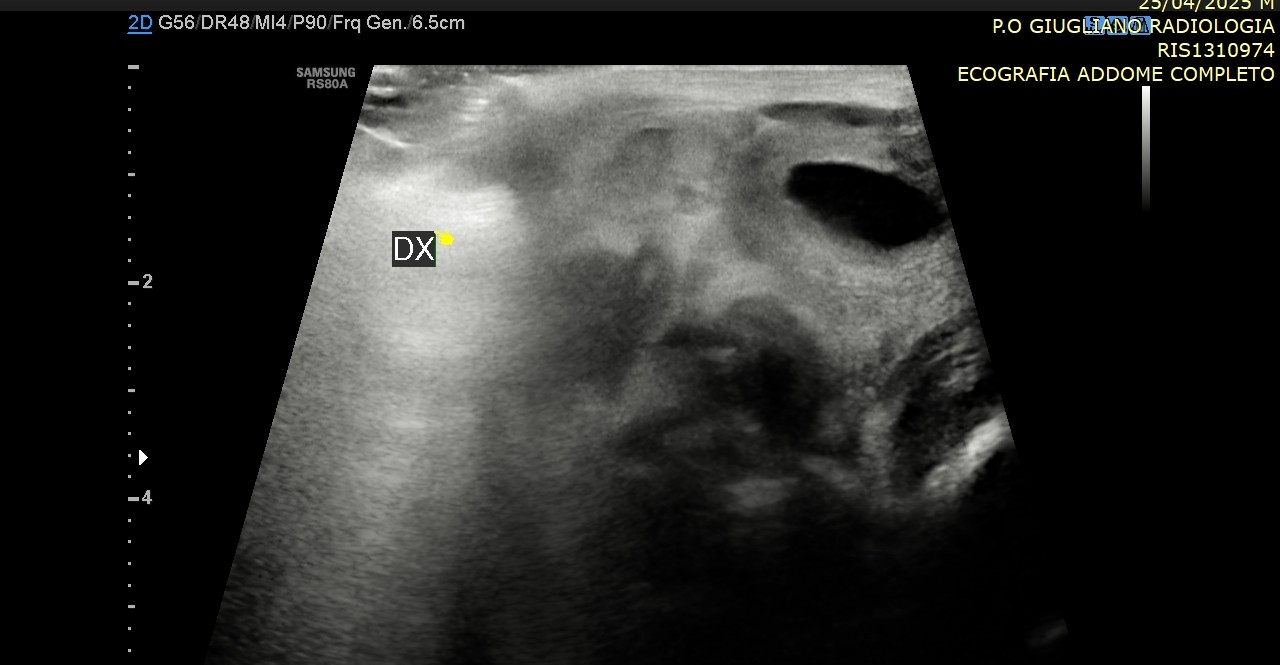

La diagnosi si basa innanzitutto sull’esame obiettivo del neonato o del bambino, affiancato quando necessario da indagini ecografiche o laparoscopiche. Il trattamento di scelta è chirurgico, tramite orchidopessi, e dovrebbe essere eseguito precocemente, idealmente tra i 6 e i 12 mesi di età, per ridurre al minimo i rischi futuri.